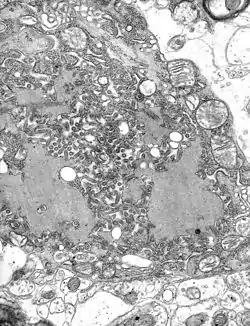

An RNA virus is a virus—other than a retrovirus—that has ribonucleic acid (RNA) as its genetic material.[1] The nucleic acid is usually single-stranded RNA (ssRNA) but it may be double-stranded (dsRNA).[2] Notable human diseases caused by RNA viruses include the common cold, influenza, SARS, MERS, COVID-19, Dengue Virus, hepatitis C, hepatitis E, West Nile fever, Ebola virus disease, rabies, polio, mumps, and measles.